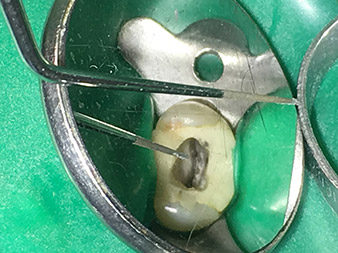

Dr. Nouraie: Yes, in my opinion. The tips allow you to work in a particularly atraumatic and minimally invasive manner. Among other steps, this applies to the exposure of the individual canal accesses, preparation of the cavity in the area of the pulp chamber, rounding off of the canal openings at the transition from the bottom of the chamber to the root canal and preparation of the coronal regions of the root canals.

Dr. Nouraie: I particularly enjoy working with the 1E tip. It is perfectly suited to activating the rinsing fluid in the root canal system. The delicate design of the tip allows you to reach deep sections of the canal too and ensure optimal activation.

The 4E tip – this instrument is optimally suited to preparation of the cavity floor at the transition to the canals. It can be used to round off the transition between the canal and the cavity floor optimally so as to produce a funnel leading into the canal. In addition, the instrument is the ideal choice for removing dentine overhangs from canals.

All in all, the cavity can be prepared very efficiently and minimally invasively with this tip by optimally rounding off and smoothing overhangs, corners and edges.